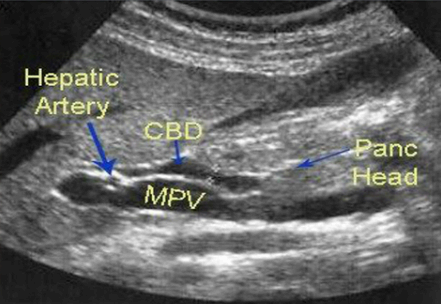

총담관(CBD) 확장 시 간동맥 (hepatic artery) 이 보이는 단면에서 wall 은 제외하고 측정한다. 총담관을 측정할 때 간동맥은 랜드마크가 된다.

- 총담관(common bile duct)의 직경은 7mm를 초과하지 않는다 (예외: 고령자, cholecystectomy 인경우 7~11mm 정상으로 간주한다.)

- 총 간관(common hepatic duct)은 4mm보다 작다.

- 간외담관(extrahepatic bile duct)은 총 간관(CHD)과 총담관(CBD)으로 나뉘고 그 끝은 십이지장 내 유두부이다.